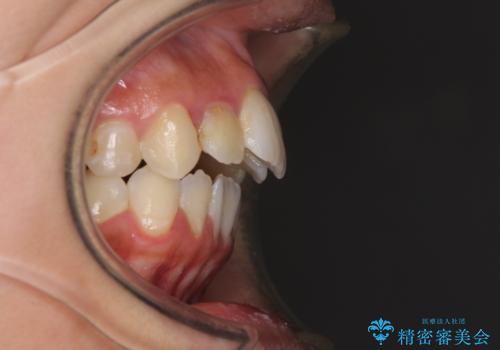

元々むし歯の処置歯が多く、神経を取り除いている歯が多くありましたが、どうやら右上の前歯と小臼歯は外傷により神経を失った可能性があり、抜歯したスペース前後の歯が全く動かない状態でした。

結果として下顎の小臼歯は抜歯せず、右上の抜歯スペースはむし歯処置を兼ねてオールセラミックブリッジにて補綴治療を行うこととしました。

動かない歯での停滞や、出産と子育てなどにより治療期間は長期化しましたが、整った歯列にて仕上げることができました。